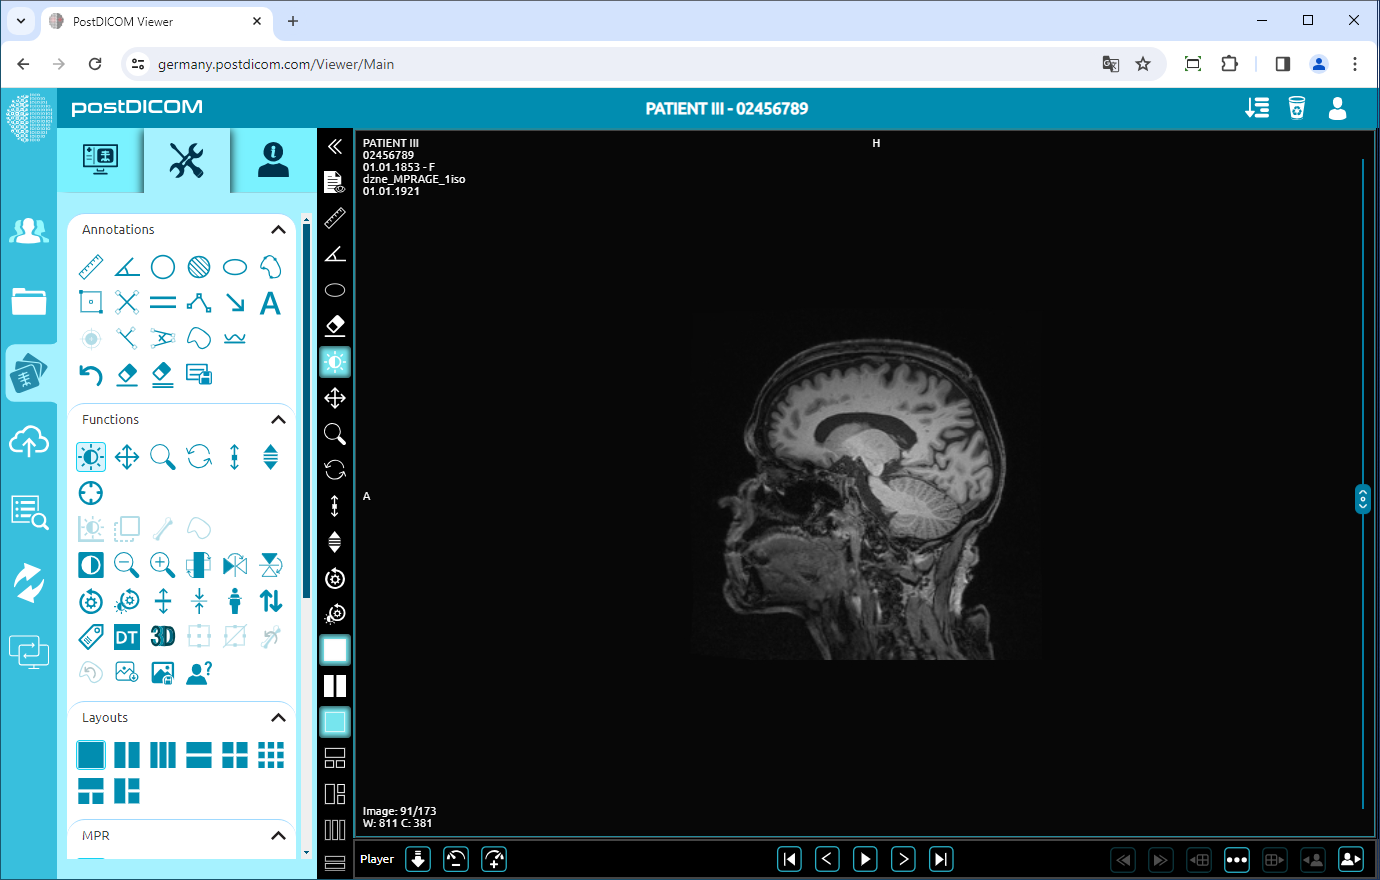

To zoom out the image by one level, click on “Zoom Out” icon on the left side of the page.

After clicking, you will see that the image will be one level smaller. The more you click, the image will be smaller.

Reset

Click on the “Reset” icon on the left side of the page. After you click on the icon, you will reset all the functions activities on the image and return to the original image.